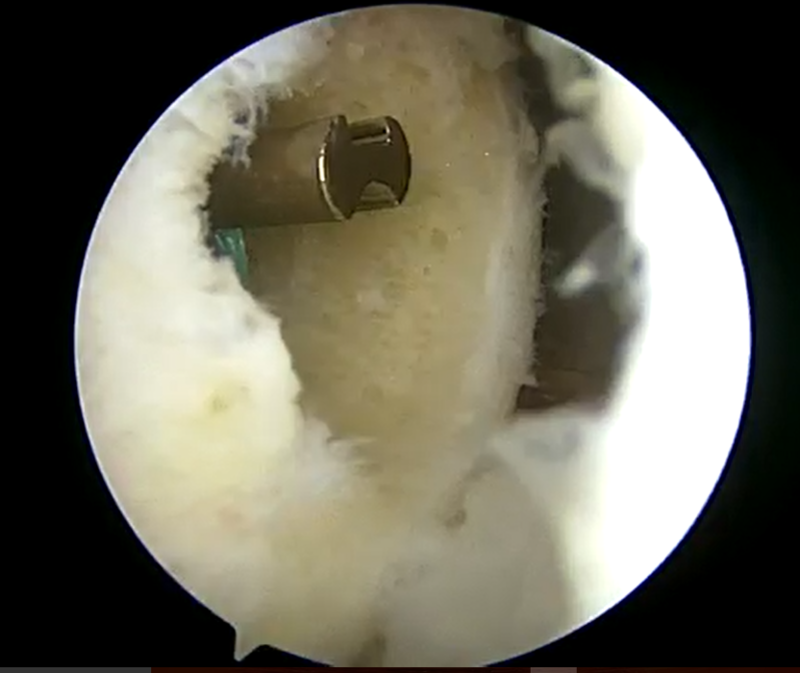

手術所見

![]() ![]() | ![]() ![]() | ![]() ![]() |

| 前十字靭帯損傷部 | 大腿骨側骨孔作成 | 脛骨骨孔作成 |

| 外側半月板問題なし | 内側半月板問題なし | 再建靭帯 |